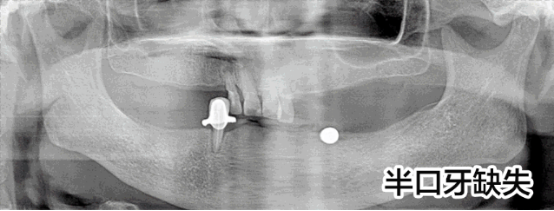

半口牙種植修復(fù)案例

病例簡介:周女士,女,57歲,家住泉州,因下半口牙在當(dāng)?shù)胤N植不成功而來我院就診。

劉斌元教授在為該患者做了詳細(xì)的檢查后表示:“周女士由于先前種植牙的失敗,造成對口腔牙槽的破壞比較嚴(yán)重,需要重新做手術(shù)修整牙槽”

決定種植方案后,劉斌元教授分別為周女士做了三次診療,第一次做電腦種植前準(zhǔn)備;第二次做電腦種植手術(shù),覆蓋義齒恢復(fù);第三次做固定義齒修復(fù)。目前周女士的半口牙齒已種植完畢,果很好。